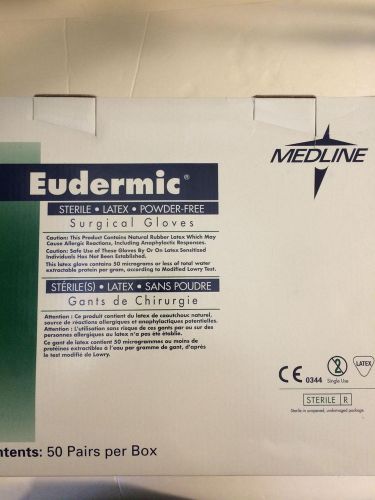

Medline Eudermic Latex Powder Free Surgical Gloves size 8 box of 50 pairs